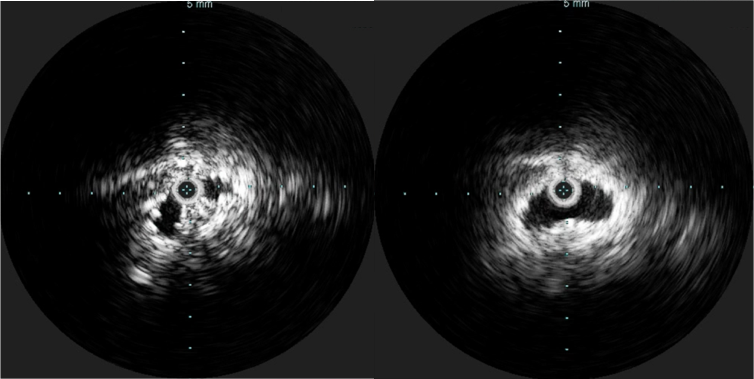

Completion venography suggested successful iliocaval recanalization and revascularization but these procedures are not done without a final intravascular ultrasound (IVUS).

Looks done, but needed final intervention after IVUS.

Intravascular ultrasound revealed incomplete expansion of the right common femoral stent. This was treated with another stent and ballooning with the result on the right.

Stent compression on IVUS treated with second stent

Venography alone is insufficient in determining patency. As illustrated, IVUS ensures a durable outcome.